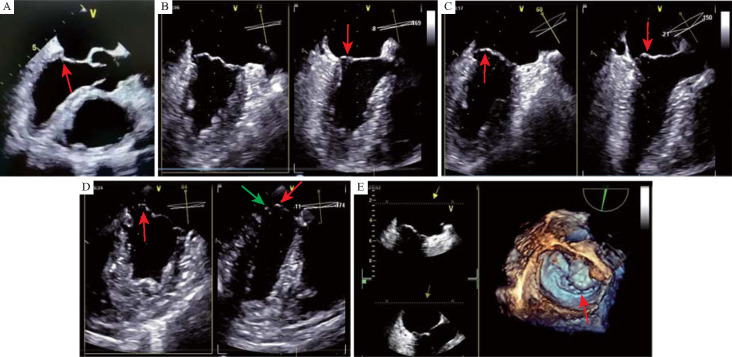

Methods: The study group comprised of thirty-two adult patients with atrial septal defect who underwent thoracoscopic repair surgery at the First Affiliated Hospital of the Air Force Medical University from March to September 2022. Two-dimensional and real-time three-dimensional transesophageal ultrasonography of the mitral valve were performed after anesthesia. The parameters of the mitral valve structure at the late diastolic and late systolic stages were recorded, including anteroposterior and left-right annular diameters, anterior and posterior valves lengths, the vertical distance from the coaptation point of leaflet zone 2 during systole to the annular plane (mitral valve coaptation depth) and mitral valve coaptation length. Data from 32 patients with normal intracardiac structure and no mitral valve regurgitation (control group) were also collected and compared with those of the study group. Concurrent mitral valvoplasty was performed during the atrial septal defect repair surgery for 7 patients with significant mitral valve structural abnormalities and 2 patients with significantly increased mitral regurgitation after cardiac resuscitation. The study group was followed up with transthoracic echocardiography for 2 years postoperatively.

Results: In the study group, 26 (81.3%) patients had varying degrees of mitral valve morphological abnormalities. Among them, 10 (31.3%) patients had short mitral valve coaptation length or depth, 12 (37.5%) patients had closure point malposition, and 4 (12.5%) patients had different bulge of anterior and posterior leaflets. Compared with the control group, the study group had significantly smaller systolic and diastolic mitral left-right annular diameter, mitral posterior valves lengths, mitral coaptation length or depth (all P<0.05), a higher pulmonary systemic flow ratio (P<0.01), and a lower maximum blood flow velocity across the mitral valve (P<0.05). After 2 years of follow-up, among the 9 patients who underwent concurrent mitral valvoplasty, the mitral valve maintained no or little regurgitation, and the average mitral valve pressure difference was less than 5 mmHg (1 mmHg=0.133 kPa). Among the 23 patients without concurrent mitral valvoplasty, 2 patients had moderate regurgitation 1 year after surgery, with a pulmonary/systemic flow ratio larger than 2.8.

Conclusions: Patients with large atrial septal defects often have abnormal mitral valve structure. Therefore transesophageal echocardiography is recommended for mitral valve assessment during the surgery. If significant mitral valve structural abnormalities are detected, concurrent mitral valvoplasty is recommended.

目的:探讨经食管超声心动图评价二尖瓣在房间隔缺损修复术中的应用。方法:收集2022年3月至9月在空军军医大学第一附属医院行胸腔镜下房间隔缺损修补术的成人患者32例(研究组)。麻醉后行经食管二尖瓣二维及实时三维超声检查。记录舒张晚期和收缩期二尖瓣结构参数,包括前后、左右环直径、前后瓣长度、收缩期小叶2区吻合点到环平面的垂直距离(二尖瓣吻合深度)、二尖瓣吻合长度。同时收集32例心内结构正常、无二尖瓣返流的患者(对照组)的上述数据,并与研究组进行比较。对7例二尖瓣结构明显异常及2例心脏复苏后二尖瓣返流明显加重的患者在房间隔缺损修复术中行同期二尖瓣成形术。术后随访2年经胸超声心动图。结果:研究组有26例(81.3%)患者有不同程度的二尖瓣形态异常,其中10例(31.3%)患者二尖瓣闭合长度或闭合深度短,12例(37.5%)患者有闭合点错位,4例(12.5%)患者有前后小叶不同程度的凸出。与对照组相比,研究组的收缩期和舒张期二尖瓣左右环直径、二尖瓣后瓣长度、二尖瓣覆盖长度或覆盖深度均明显小于对照组(均为ppp)。房间隔缺损较大的患者常合并二尖瓣结构异常,术中建议经食管超声心动图对二尖瓣进行评估,如有明显的二尖瓣结构异常,可同时行二尖瓣成形术。